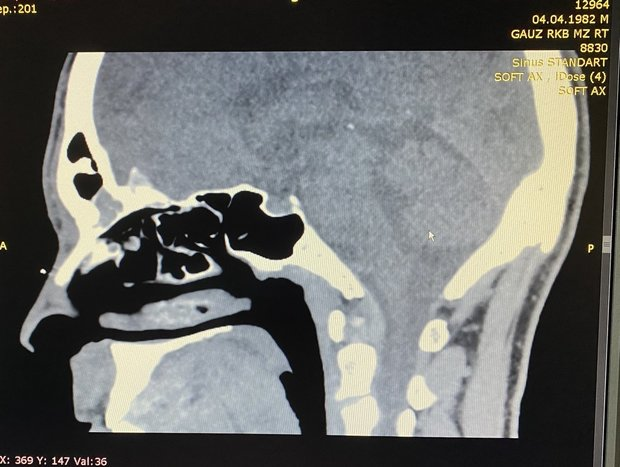

In the case of a runny and congested nose, Marat Gilyalov recommends using sprays or drops but for no more than 3-5 days, then it will be possible to avoid complications like sinusitis and other diseases. If rhinitis persists for more than a week, first of all, turn to a specialist or your GP who can determine if there is a complication with the help of tests and angiography and change treatment tactics.